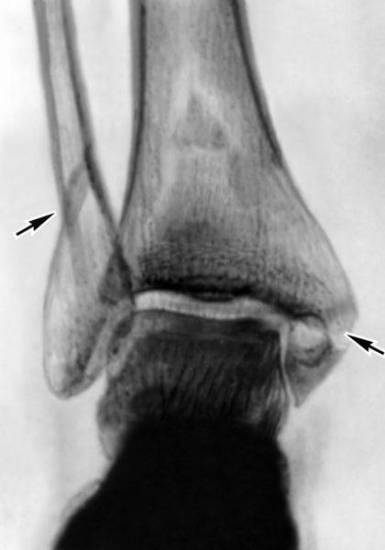

Болезненные ощущения в голеностопе связаны с повреждением связок или одной из костей – большеберцовой, малоберцовой, таранной. Проблемы в этой области ног, появляющиеся, на первый взгляд, без причин, становятся следствием, как чрезмерных физических нагрузок, так и скрытых патологий.

- Переломом. После травмы лодыжка быстро опухает. При прощупывании пострадавший чувствует достаточно сильную боль. Из-за перелома стать на ногу не представляется возможным.

- Вывихом или подвывихом. От них зачастую страдают люди, имеющие слабые связки или лишние килограммы. Ослабленный связочный аппарат значительно увеличивает риск получения вывиха без видимых причин.